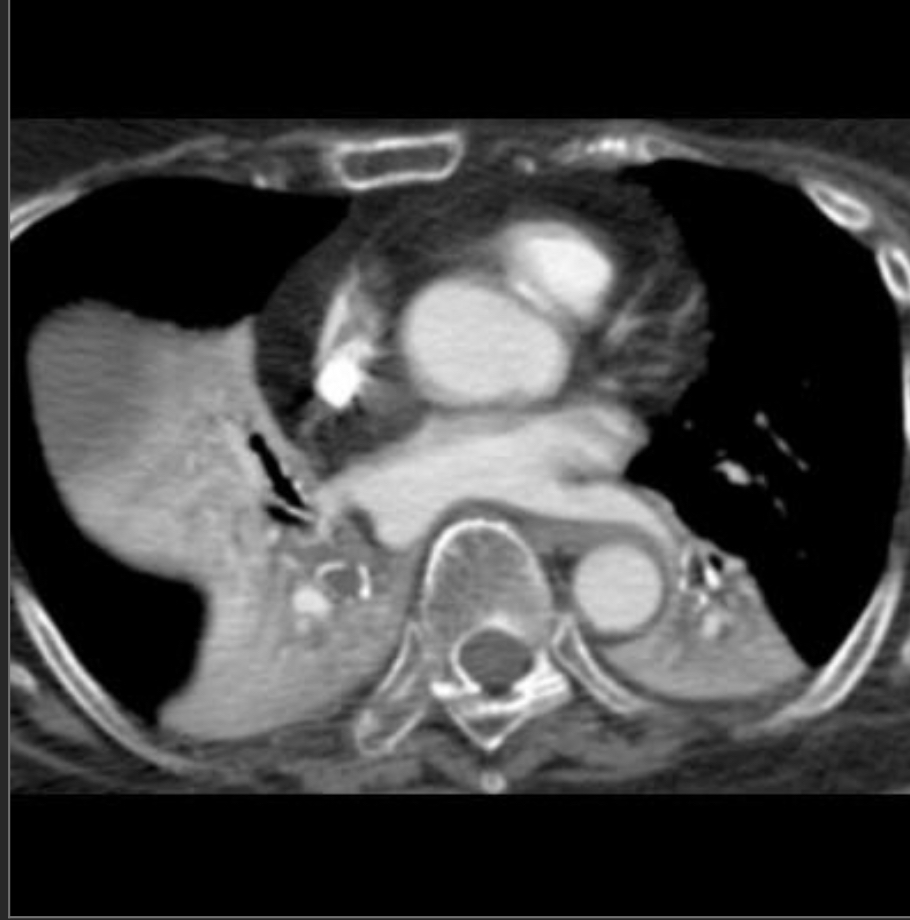

43yo F with SLE presents with dyspnea

Pericardial Effusion

cardiac shadow is enlarged but the pulmonary vessels are not dilated –> suspect a pericardial effusion.

azygous vein and SVC may be dilated, reflecting the elevated central venous pressure necessary to maintain right ventricular filling.

mediastinal interface over the left hilum in the absence of enlargement of the pulmonary arteries should also alert you to possibility of a pericardial effusion (fluid accumulating in a pericardial recess) because an enlarged cardiac chamber, such as the left atrial appendage, will not produce an interface this high along the left cardiac border.